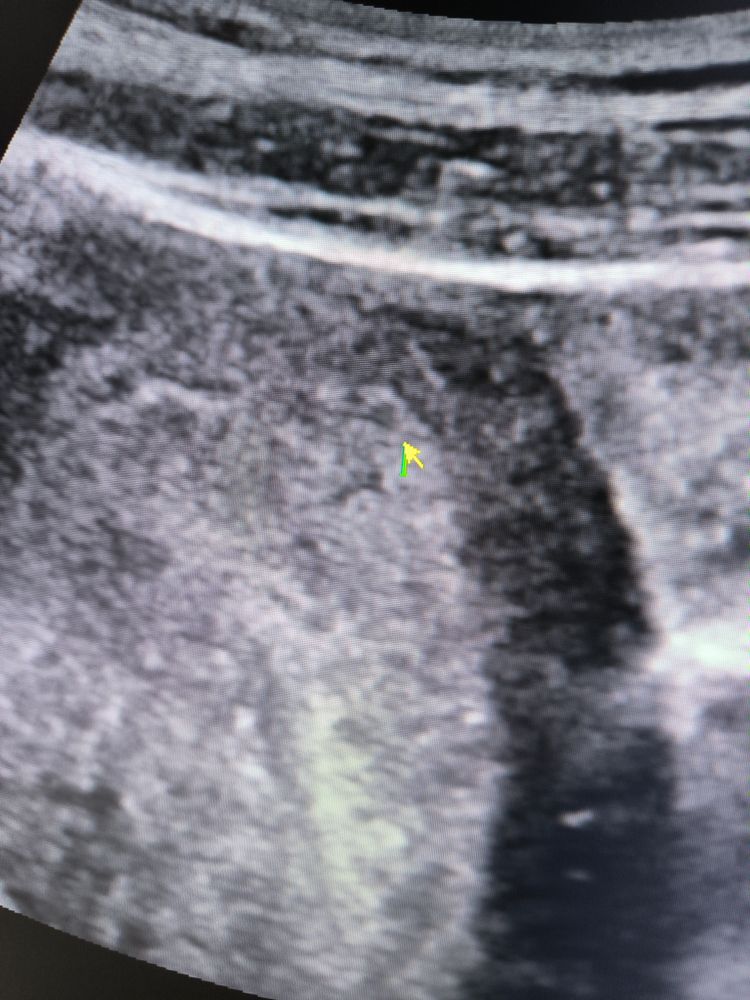

УЗИ 4 Нед 4 дня

Рано пошли... Что то не похоже на яйцо

Либо аппарат не очень хороший

Это не пя